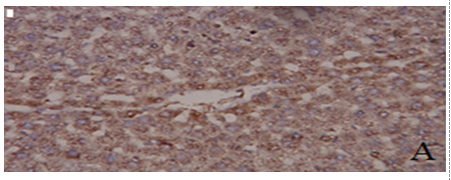

Fig. 5: Photomicrographs of liver tissue. Where A) represents control, B) aluminum chloride (AlCl3), C) zinc oxide nanoparticles (ZnO NPs) and D) aluminum chlorid (AlCl3)+zinc oxide nanoparticles (ZnO NPs)

Effect of ZnO NPs and/or AlCl3 treatment on liver histopathology

As shown in fig. 5, the control group exhibited normal hepatocytes architecture showing well-defined central nucleus and abundant cytoplasm, while the hepatic tissue of the AlCl3-intoxicated animals indicated as previously recorded [5] by alterations in hepatic histo-architecture after 6 w of treatment evidenced by disrupted central vein and disarrangement of hepatic cords at most of the places and, also, vacuolated hepatocytes, leukocytes infiltration and many Kupffer cells and hepatocytes with dense and pyknotic nuclei were observed. ZnO NPs administration to animals for 6 w also showed vacuolization and disrupted hepatic cords.

While ZnO NPs+AlCl3 treated group indicated revealed that pre-administration of ZnO NPs preserved, to some extent, the hepatic tissue from these pathological alterations caused by AlCl3 exposure.